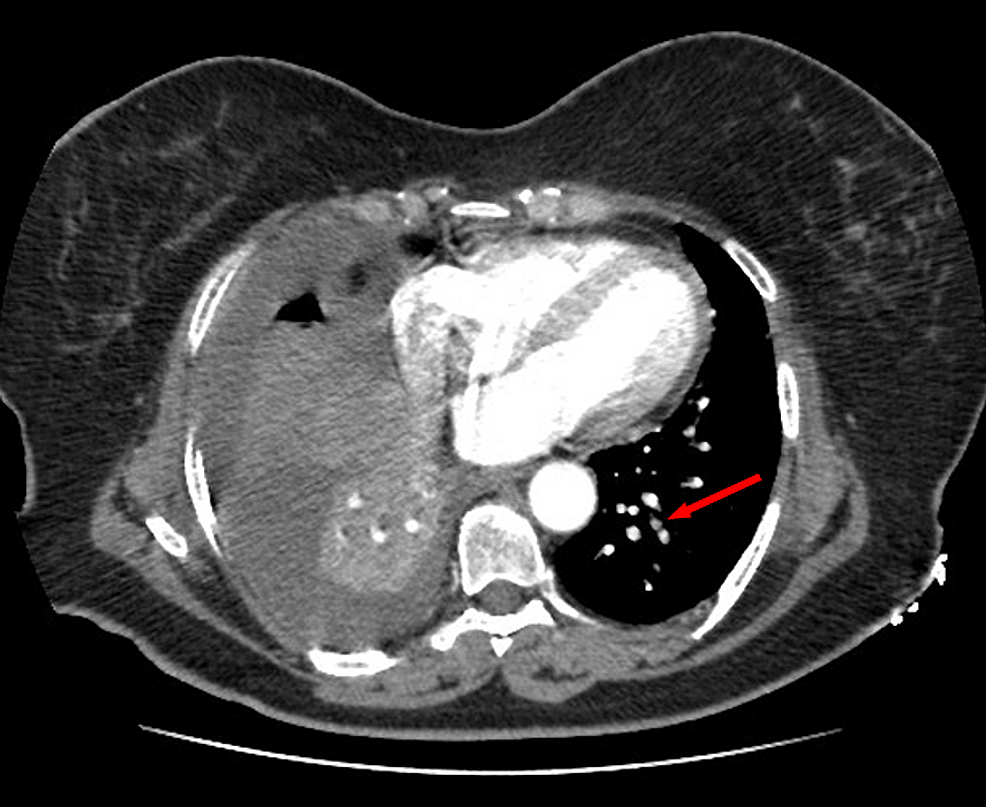

A 59-year-old woman was admitted to the emergency department with sudden onset of chest pain for five hours. She had hypertension (treated with β-blockers) as a cardiovascular risk factor. She was diagnosed with advanced non-small-cell lung cancer with liver metastases one month previously. The patient was not considered for surgical resection, she was scheduled for chemotherapy, and, consequently, no antineoplastic treatment had been initiated yet. Prophylactic anticoagulation was not indicated On clinical examination, her blood pressure was 150/90 mmHg with a pulse of 100 beats per minute, oxygen saturation of 95%, and normal heart sounds. The 12-lead electrocardiogram showed sinus rhythm with a heart rate of 102 beats for minutes and ST-segment elevation in all leads except aVR where ST-segment depression was noted (Figure 1). Her laboratory test results revealed a baseline troponin T level of 1212 ng/ml (normal range < 26 ng/ml). Also, the echocardiography findings revealed akinetic walls from the mid to apical septum and anterior and inferior walls. The ejection fraction was estimated to be 39%. Therapy was started with clopidogrel, aspirin, and low-molecular-weight heparin. The patient underwent a coronary angiogram from the right radial approach, which revealed the presence of an extended thrombus in the left anterior descending artery (LAD), and another thrombus was found in the second segment of the right coronary artery (RCA) with thrombolysis in myocardial ischemia (TIMI) III flow and without any atherosclerotic lesions in the coronary artery tree (Figure 2 and Figure 3), therefore, balloon angioplasty and/or stent placement was not considered. The patient was taken to the coronary care unit (CCU) and tirofiban infusion was administered for a period of 48 hours. In view of persistent breathlessness, pulmonary embolism was suspected. There were no symptoms or clinical signs suggestive of deep venous thrombosis. A computed tomographic pulmonary angiography was performed and showed a distal pulmonary embolism (Figure 4). The patient was discharged on acenocoumarol to be followed as an outpatient. At her 45 days follow-up, she did not report any episode of chest pain, bleeding, as well as any thrombotic events.